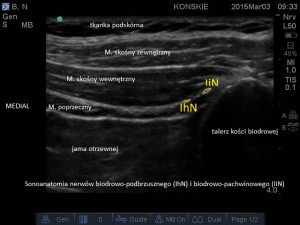

W celu lokalizacji nerwów liniową głowicę USG przykładamy w linii łączącej grzebień kości biodrowej z pępkiem (ok. 5 cm dogłowowo i grzbietowo w stosunku do kolca biodrowego przedniego górnego -ASIS), następnie lokalizujemy trzy warstwy mięśni, kolejno idąc od góry: mięsień skośny zewnętrzny, wewnętrzny oraz poprzeczny. Nerwy IiN i IhN na tym poziomie przebiegają w przestrzeni TAP i w obrazie ultrasonograficznym przybierają postać okrągłych hipoechogenicznych struktur. W pobliżu nerwów, w tej samej przestrzeni powięziowej, przebiega tętnica głęboka okalająca biodro, która może być przydatna w celu ich lokalizacji. Można ją odnaleźć używając opcji color Doppler.

- Sonoanatomia nerwów biodrowo-podbrzusznego (IhN) i biodrowo-pachwinowego (IiN)

- Sonoanatomia nerwów biodrowo-podbrzusznego (IhN) i biodrowo-pachwinowego (IiN)